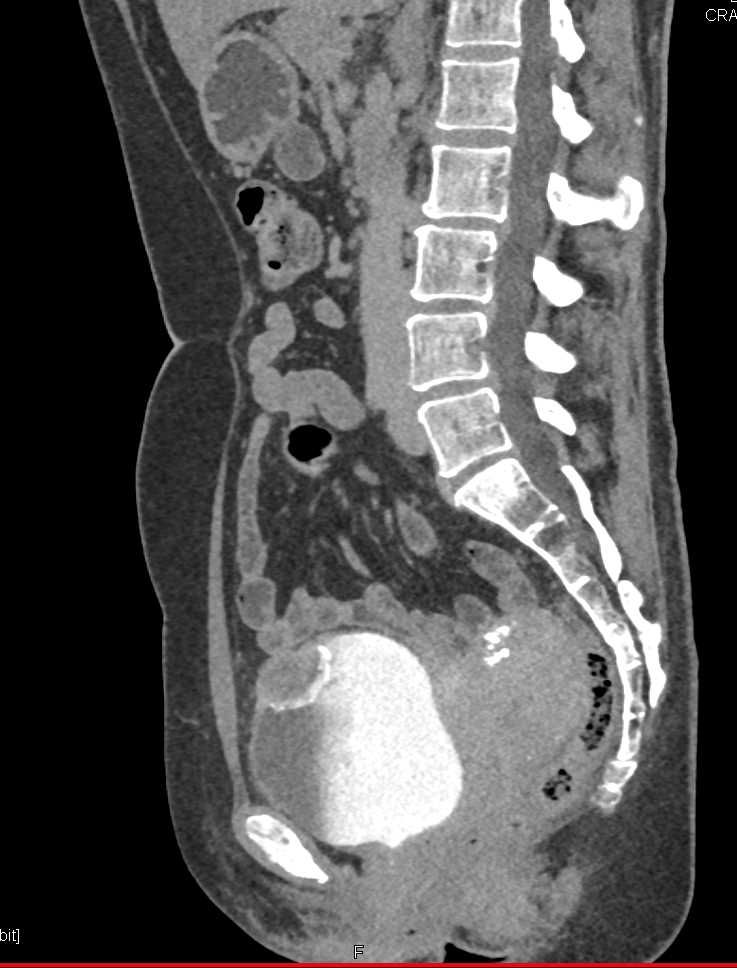

Urachal Carcinoma of the Bladder